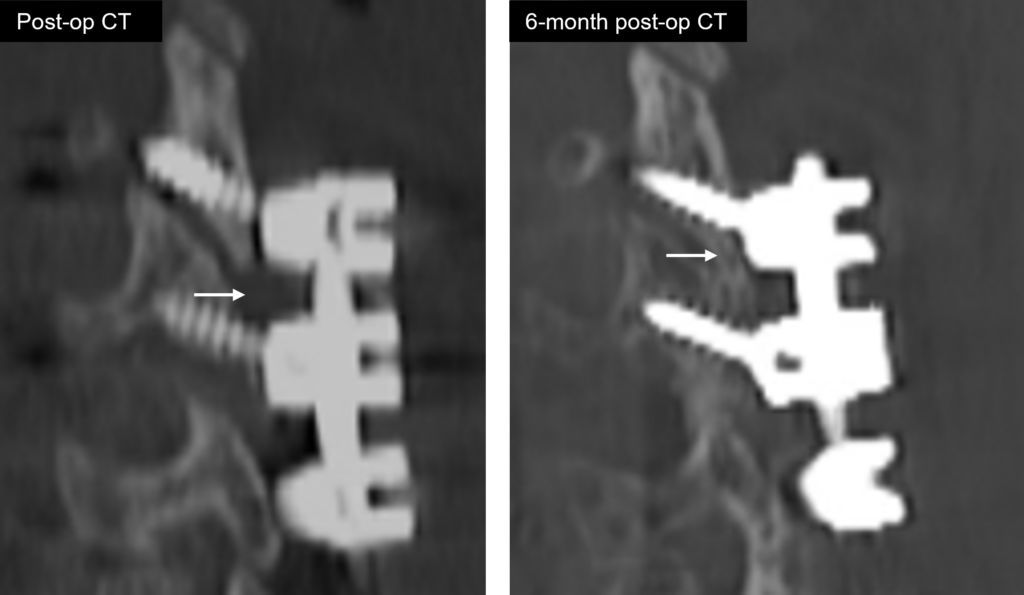

Fuse

FLASH Facet Pellets contain Accell Technology for immediate and sustained release of growth factors4

Post-op CT shows centered decortication

Fusion identified in the facet joint by CT at 10 months